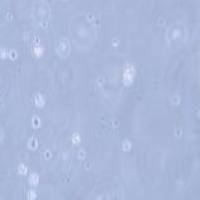

半贴壁半悬浮

2) 形态:半贴壁半悬浮